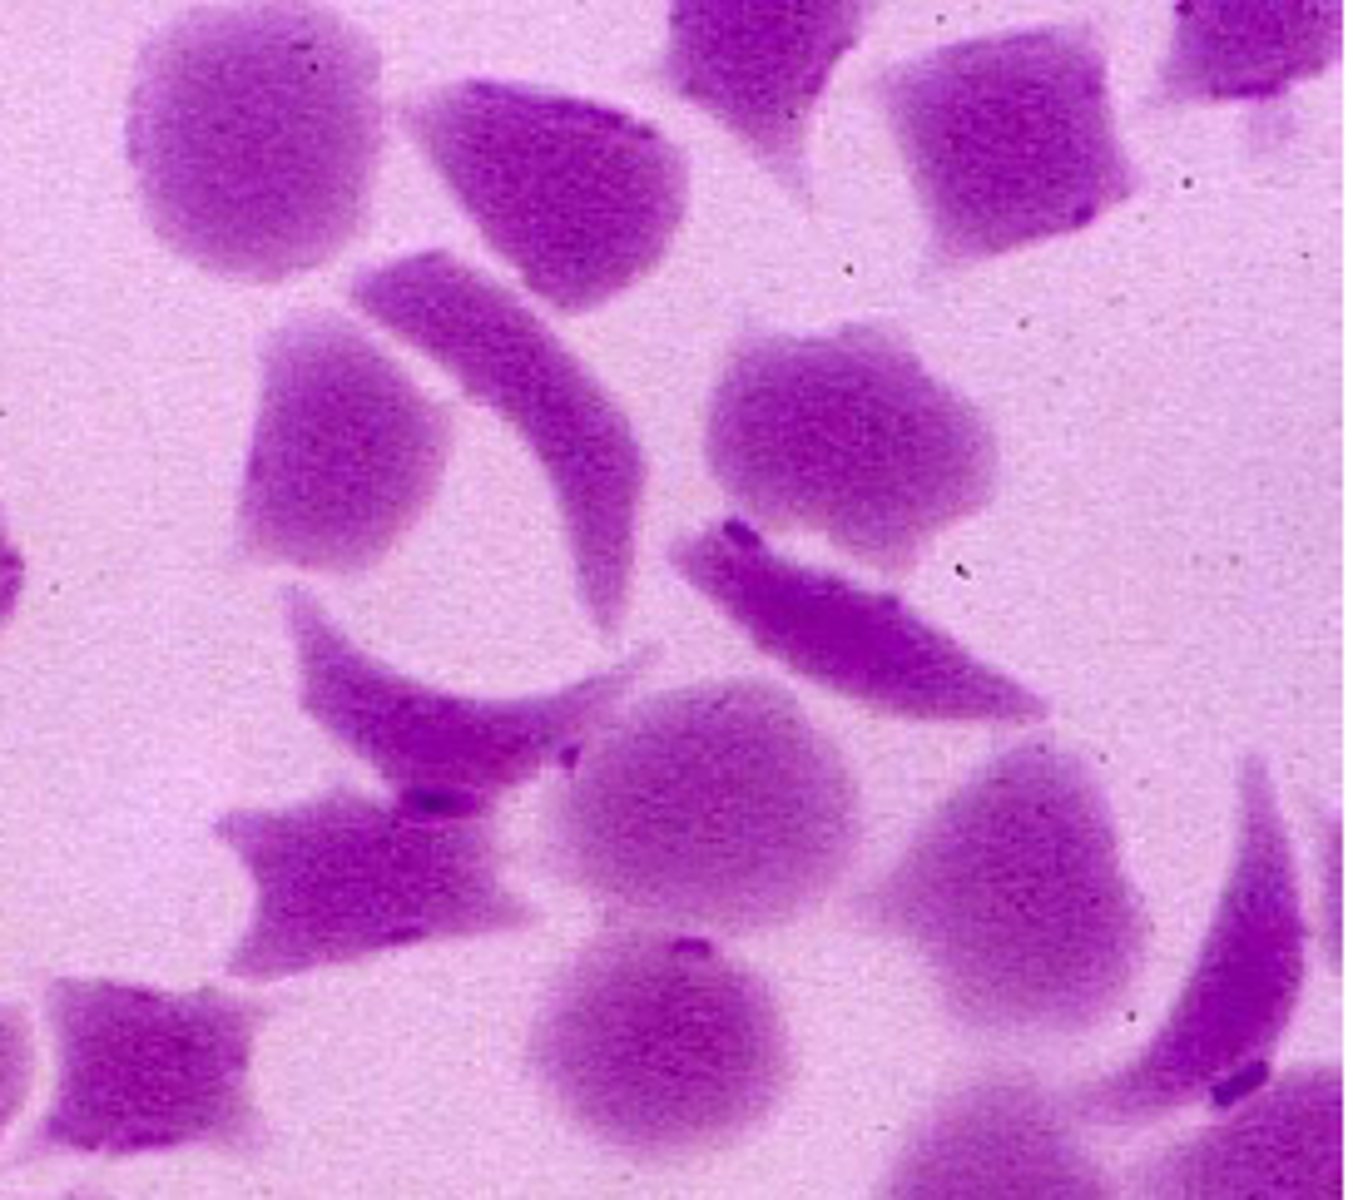

sickle shaped RBC AKA drepanocyte

deer